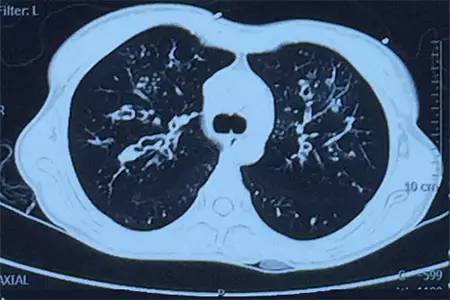

肺CT見下圖

該患者肺部影像學(xué)表現(xiàn)為明顯的支氣管擴(kuò)張,同時(shí)伴有彌漫的滲出斑片影,考慮合并感染,細(xì)菌學(xué)培養(yǎng)提示為綠膿桿菌,結(jié)合藥敏結(jié)果給予頭孢他啶+阿米卡星抗感染,患者存在II型呼吸衰竭予氣管插管機(jī)械通氣支持,加強(qiáng)體位引流排痰,治療18天,患者情況好轉(zhuǎn)出院。